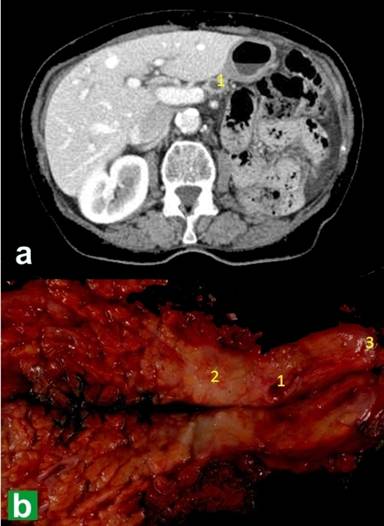

After 11 months of follow-up, a control CT-scan of the abdomen detected a 2 cm enlargement of the distal main duct of the pancreatic remnant with a sharp change in its caliber and without any apparent mass effect. Endoscopic ultrasound showed a nodular lesion of 15 mm diameter in the neck of the pancreas obstructing the duct; endoscopic ultrasound-guided cytology indicated a PADC. Another staging study ruled out distance metastasis, and so a complete resection of the pancreatic remnant was performed, consisting in a pylorus-preserving PD extending to the left pancreatic remnant via laparoscopic approach (Figure 4). The patient was placed in the supine position with the legs apart, the standard position used by our group for laparoscopic PD. Reconstruction of the digestive tract was performed with a single loop ascending behind the mesentery for the end-to-side hepatico-jejunostomy, which was anastomosed with two continuous polyglycolic acid 4/0 sutures. The end-to-side antecolic duodeno-jejunostomy was performed with interrupted polyglycolic acid 3/0 sutures. An iterative transversal suprapubic incision was performed for the removal of the resection specimen via an extraction bag (Figure 2). Operative time was 397 minutes.

Figure 4. Diagnostic imaging and resected specimen for pancreaticoduodenectomy. a. Abdominal CT showing dilatation of the pancreatic duct (1). b. Surgical resection specimen: (2) pancreatic tumor, (3) distal margin of the pancreatic remnant. |

In the postoperative period the patient presented chylous ascites and required hospitalization for 17 days. No transfusion was required. As in the previous pancreatic resection, the definitive biopsy of this new tumor showed a new PADC with other PanIn 2 and 3 lesions in the rest of the gland. Probably, this new PADC had been present in the first operation as a PanIn 3 lesion. Two out of 21 nodes isolated were found to be affected. No chemotherapy was administered after the second operation. The patient has insulin-dependent diabetes mellitus. Although 31 months after the first pancreatic resection the patient is alive, local recurrence was detected 26 months after the first operation.